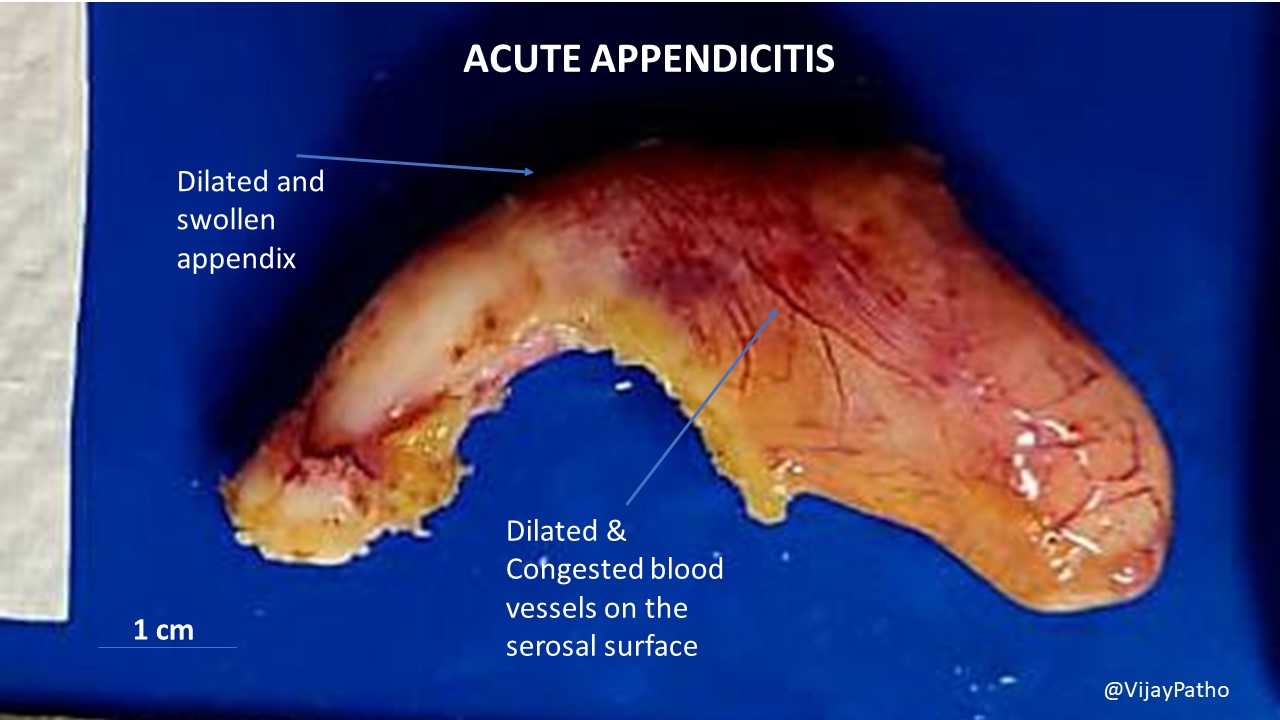

The appendix is a finger-shaped pouch that sticks out from the colon on the lower right side of the belly, also called the abdomen. Appendicitis causes pain in the lower right abdomen. However, in most people, pain begins around the belly button and then moves. As inflammation worsens, appendicitis pain typically increases and eventually.

Appendicitis is an inflamed appendix. It can cause acute (sudden, intense) pain in your lower abdomen. Your appendix is a small, tubular pouch, about the size of a finger, that protrudes from the lower right end of your large intestine. Poop (feces) moving through your large intestine can block or infect your appendix, leading to inflammation.

Clinical evaluation — The diagnostic accuracy of the clinical evaluation for acute appendicitis depends on the experience of the examining clinician [ 2-7 ]. The patient presenting with acute abdominal pain should undergo a thorough physical examination, including a digital rectal examination. Women should undergo a pelvic examination.

ACUTE APPENDICITIS Pathology Made Simple